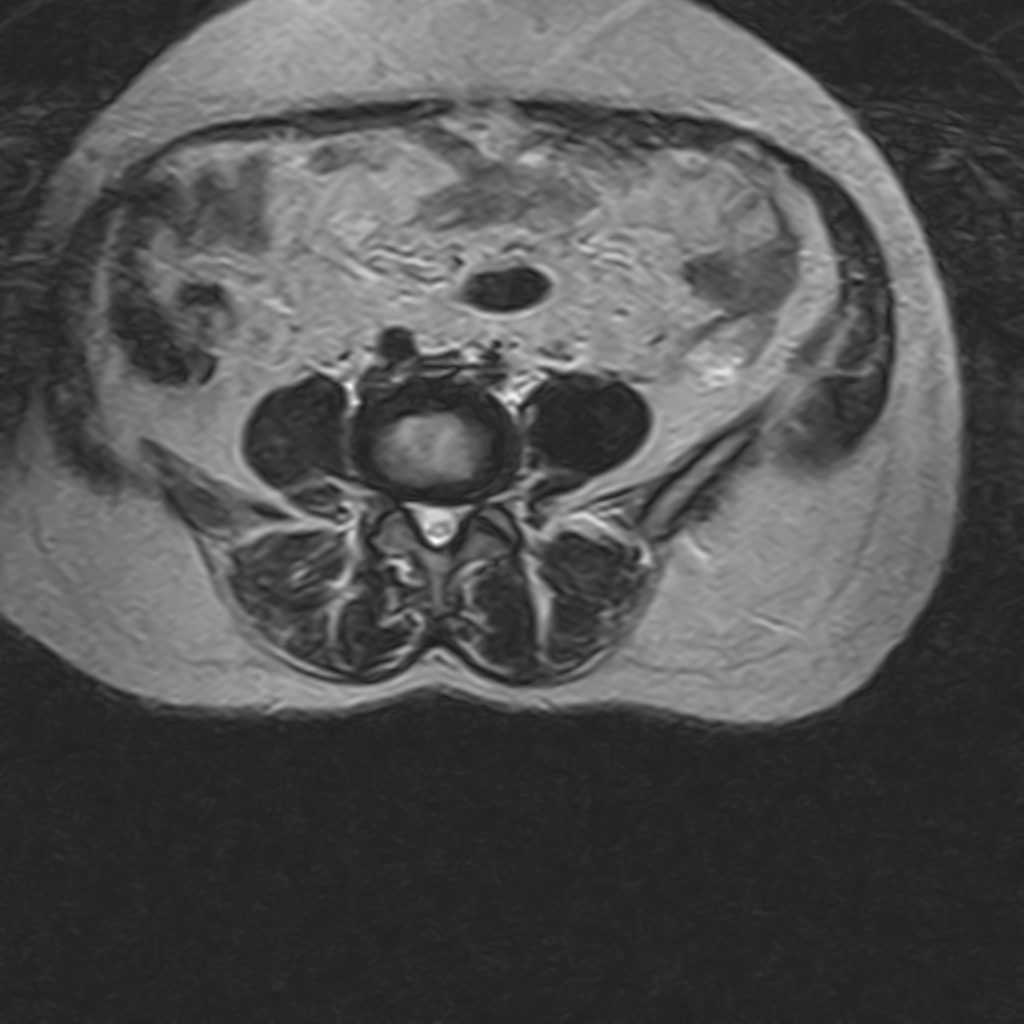

THORACIC & LUMBOSACRAL SPINE MRI

(Without contrast)

Technique : Sagittal T1 , T2 , Axial T2

REPORT:

The vertebral bodies and endplates are normal in shape and signal intensity.

The imaged soft tissues show no abnormalities .

The visualized cord and filum terminalis are normal .

The conus medullaris terminates normally at L1.

Paravertebral stripe is normal in shape and signal intensity .

– Lumbosacral hyperlordosis

– Mid thoracic spondylosis – disc space narrowing , dehydration , bulging & thecal indentation

– L2/L3 disc bulging

– L3/L4 disc space narrowing , dehydration , bulging & foramina stenosis

– L4/L5 disc bulging & canal – foramina stenosis